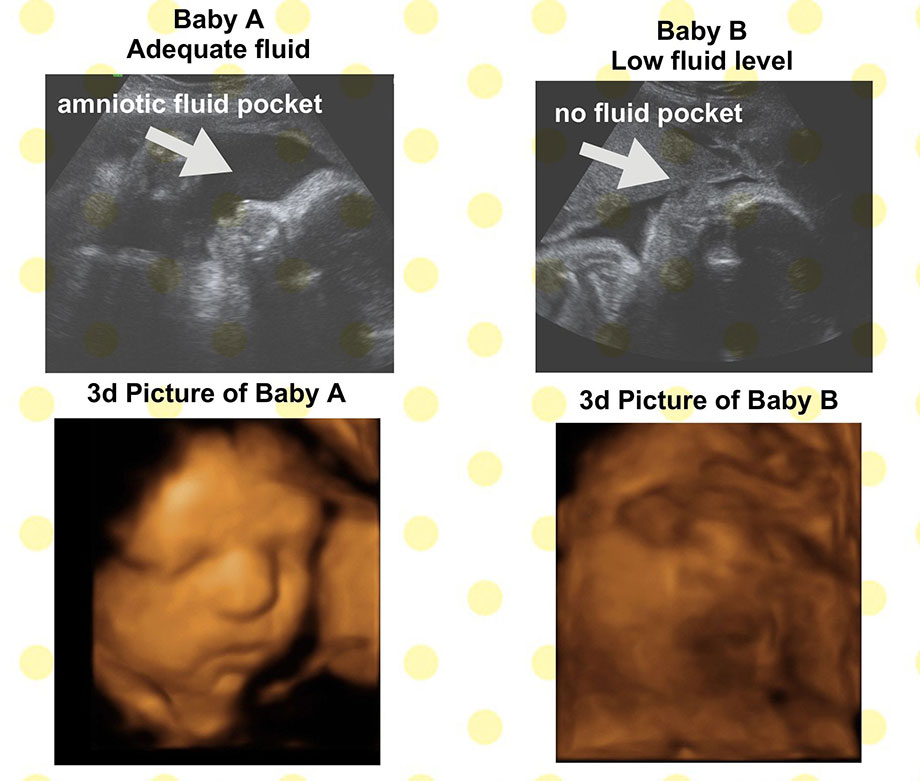

One last thing I would like to mention is you should be drinking plenty of fluid during your pregnancy! It makes a big difference in your ammonic fluid and it is recommended that everyone drink ½ ounces of water (juice or soda does not count) per pound. So if you weigh 150 pounds you should be drinking at least 75 ounces of water everyday, pregnant or not! Having plenty of fluid can be the difference between great pictures and just average pictures of your baby, not to mention that plenty of fluid is vital for your baby’s health. Our sonographers always check Mom’s fluid level with each ultrasound and it is included in our limited diagnostic exam with each ultrasound we offer.